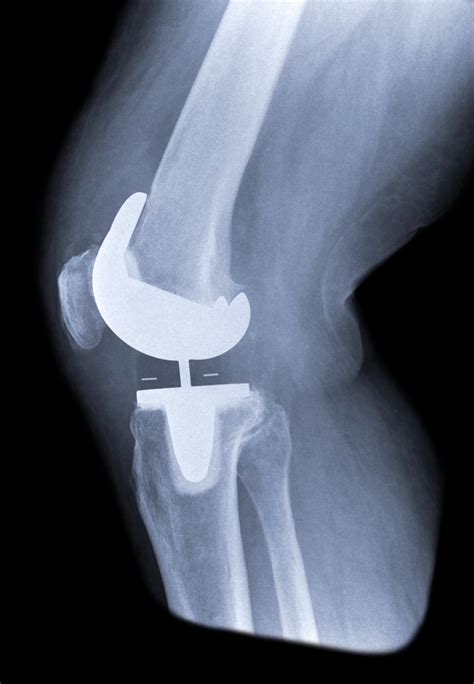

Total knee arthroplasty, or knee replacement, is a highly successful surgery designed to relieve pain and restore function in diseased or damaged knee joints. By looking at Knee Replacement Images, patients can see how an orthopedic surgeon removes the damaged cartilage and bone from the surface of the knee joint and replaces them with artificial components. These components are meticulously crafted to mimic the natural movement of a healthy knee.

• The Femoral Component: A metal piece that attaches to the end of the thigh bone (femur).

• The Tibial Component: A metal tray that sits on top of the shin bone (tibia).

• The Patellar Button: A plastic piece that replaces the surface of the kneecap.